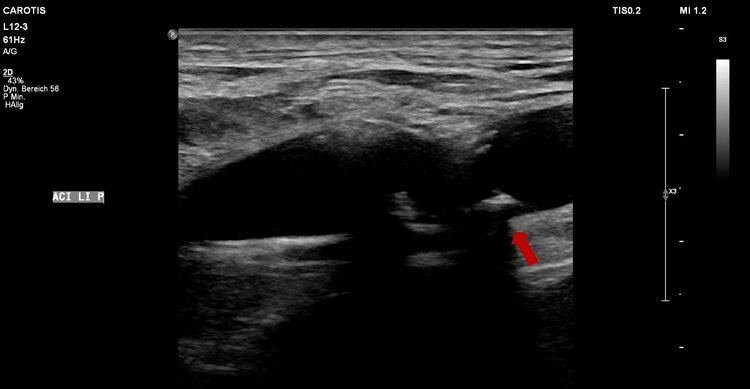

Vorbeugung und Früherkennung von Arteriosklerose (Prävention)

Durch Früherkennung und Vorbeugen (Prävention) können Gefässerkrankungen in Ihrer Entstehung verhindert oder im Voranschreiten aufgehalten werden.

Die Entstehung von Gefässerkrankungen durch eine Verkalkung der Arterienwand (Arteriosklerose genannt) wird durch viele Faktoren bedingt (s. Abbildung), vor allem durch die klassischen Risikofaktoren: Rauchen, Bluthochdruck, Diabetes mellitus und erhöhte Blutfette (Cholesterin).